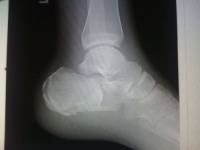

Нами наблюдался больной С., 33 лет, поступивший на лечение.После рентгенограммы был поставлен диагноз: Закрытые внутрисуставные оскольчатые переломы обеих пяточных костей со смещением отломков. Из анамнеза удалось выяснить, что травма,полученная пострадавшим в быту, является прямой. Через 2 часа после поступления под эпиду- ральной анестезией выполнили закрытый остеосинтез обеих пяточных костей аппаратом Илизарова по методике, описанной ниже.

Для этого через нижнюю треть большеберцовой кости под углом 55-60 градусов друг к другу провели две перекрещивающиеся спицы. Вторую пару перекрещивающихся под углом 35-40 градусов спиц провели через дистальный отломок пяточной кости (эти спицы были с упорными площадками, и провели их навстречу друг другу). Через тело пяточной кости во фронтальной плоскости провели спицу с упорной площадкой. Еще одну спицу провели в косо-фронтальной плоскости через I-V плюсневые кости стопы. Смонтировали аппарат Илизарова из трех внешних опор (одного кольца и двух полуколец). После репозиции костных фрагментов,которую завершили на операционном столе, для более жесткой фиксации через пяточную кость в косо-сагитальных плоскостях дополнительно провели две диафиксирующие "консольные" спицы с упорными площадками Послеоперационный период протекал без осложнений.

Ходить с легкой нагрузкой на поврежденные стопы больной начал с 3-го дня после наложения аппаратов Илизарова, с полной нагрузкой - с 25-го дня. На 40-ой день фиксации удалили спицы, проведенные через нижнюю треть большеберцовой кости и I-V плюсневые кости стопы, и были демонтированы внешние опоры (кольцо и полукольцо), на которых крепились эти спицы. Спицу, проведенную через тело пяточной кости, закрепили на оставшейся опоре (полукольце) при помощи кронштейнов. После этих манипуляций пострадавший приступил к разработке движений в голеностопных суставах.Аппараты Илизарова были сняты в следующие сроки: с левой стопы на 50 день фиксации,с правой - на 53 - получено сращение костных отломков.Отдаленный анатомо-функциональный результат лечения изучили через 1 год после окончания лечения и оценили как хороший.